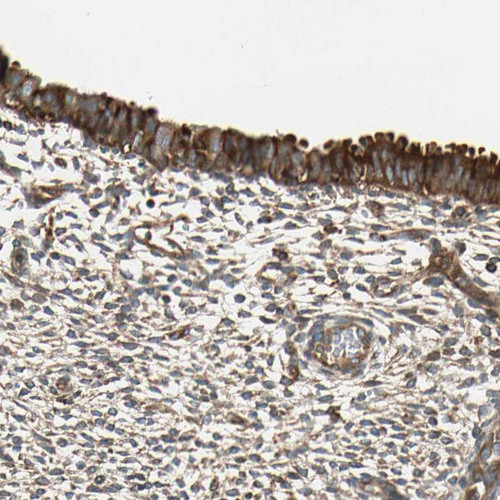

Immunohistochemistry analysis in human cerebral cortex and liver tissues using HPA008157 antibody. Corresponding TRIO RNA-seq data are presented for the same tissues.